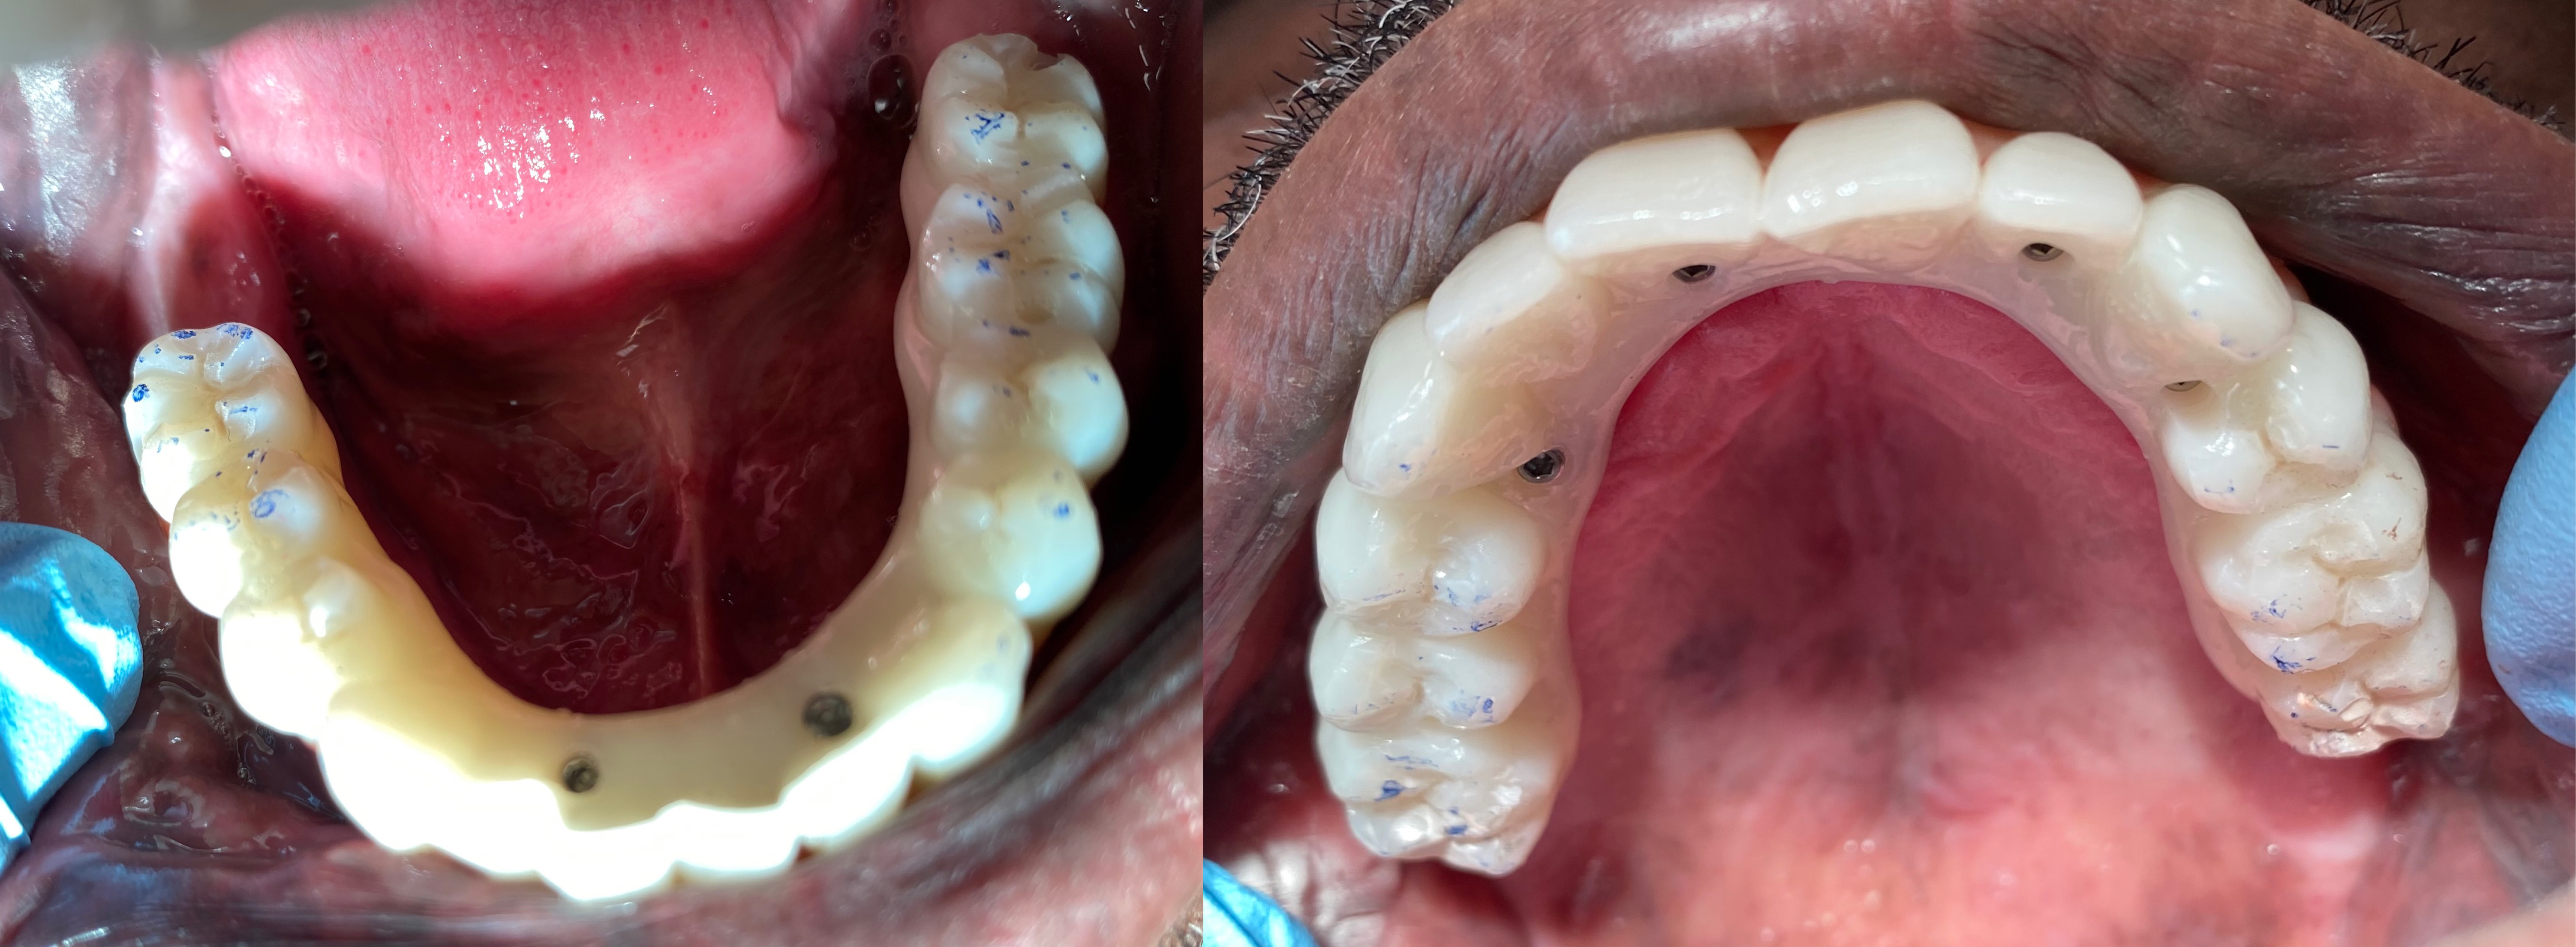

Figure 4 STL files of the full-arch restorations printed on HeyGears UltraCraft 3D Printer

Dr. Glen used an UltraCraft 3D printer to produce the full-arch dental implants in-house, reducing production time in an accurate and precise process. Dr. Glen used UltraPrint-Dental denture teeth UV resin with essential features such as high abrasion resistance and high tensile and flexural strength for implants. Its excellent durability allows it to resist corrosion from everyday products such as coffee, tea, and carbonated liquids.

Figure 5 3D printed upper and lower full-arch dental implants

With the various shades provided by the denture teeth UV resin, Dr. Glen could successfully match the ideal shades for his patient and provide treatment.